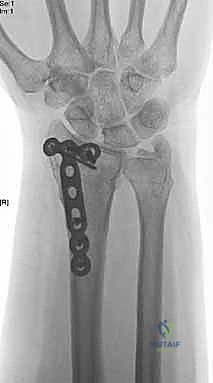

ثانياً: العلاج الجراحي (Surgical Intervention)

متى يقرر الدكتور هطيف ضرورة التدخل الجراحي؟

1. عدم الاستقرار (Instability): إذا كان المفصل الزندي الكعبري البعيد (DRUJ) غير مستقر بعد تثبيت كسر الكعبرة.

2. الانزياح (Displacement): إذا كان الكسر في قاعدة الناتئ الإبري منزاحًا بأكثر من 2 ملم.

3. الكسور المفصلية: أي كسر يخل بتطابق السطح المفصلي لرأس الزند.

4. الكسور المفتتة: في الجزء الكردوسي التي تؤدي إلى قصر عظم الزند.

خطوات التدخل الجراحي الدقيق مع الأستاذ الدكتور محمد هطيف

تُعد جراحات المعصم والزند من الجراحات الدقيقة التي تتطلب مهارة عالية، وهو المجال الذي يتفوق فيه الأستاذ الدكتور محمد هطيف بفضل استخدامه لتقنيات الجراحة المجهرية (Microsurgery) والأدوات الجراحية ذات التقنية العالية.

يقوم الدكتور هطيف بدراسة الأشعة المقطعية ثلاثية الأبعاد بدقة، ويختار نوع وحجم الصفائح المعدنية (Plates) والمسامير (Screws) المناسبة لكل مريض بناءً على حجم العظم ونوع الكسر.